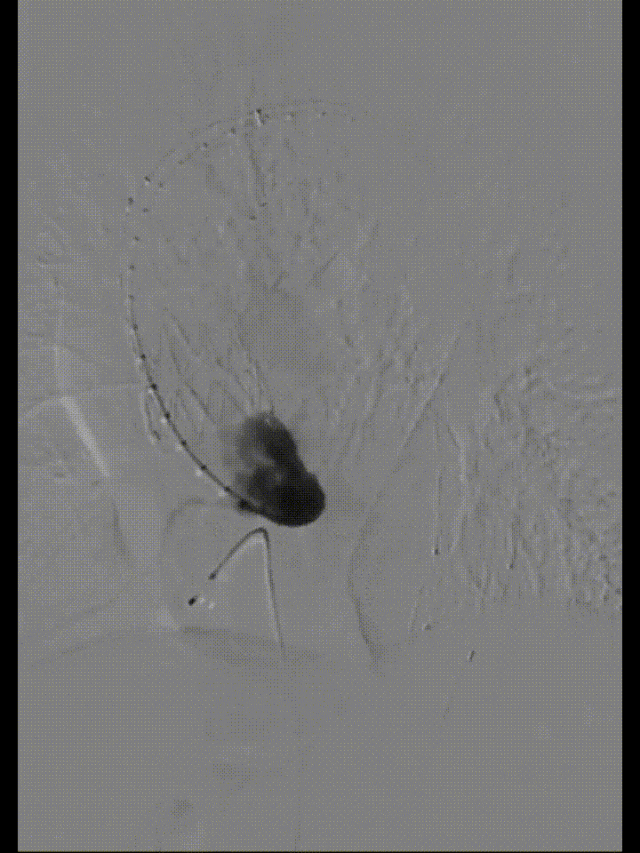

术前影像

主动脉造影后,降主动脉限制支架置入,导入近端主体支架

升主动脉后造影定位后,释放近端主体支架,术毕造影

术后复查

First In Man早期结果